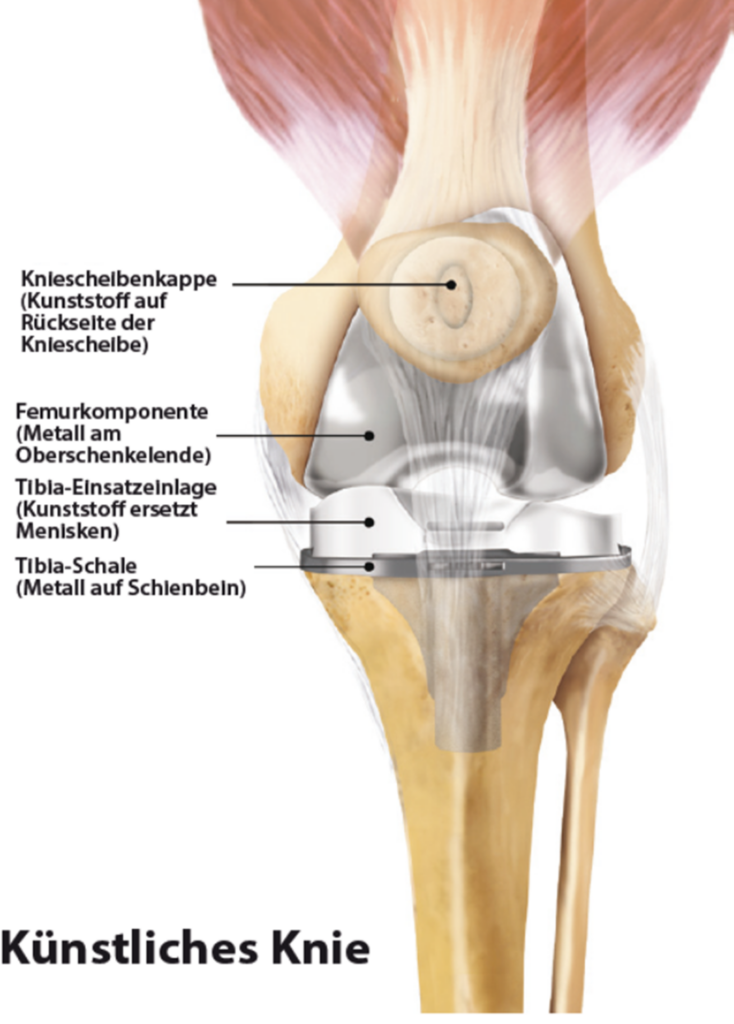

Bei der Kniegelenksarthrose wird die verschlissene Knorpeloberfläche der Gelenkpartner durch eine Metalloberfläche ersetzt („Oberflächenersatz“). Dabei wird auf den in mehreren Ebenen exakt zugesägten Oberschenkelknochen eine Metallkappe aufgeschlagen, am Unterschenkel eine dünne Scheibe mit dem verschlissenen Knorpel entfernt und mit einer Metallplatte versehen. Als Gleitschicht zwischen beiden Komponenten dient ein sog. Inlay aus Polyethylen.

Ist nur die Innenseite des Kniegelenks verschlissen, kann eine sog. Unicondyläre Endoprothese („Schlittenprothese“) eingesetzt werden.

Eine zunehmende Bedeutung kommt der Individualisierung in der Endoprothetik zu. Bereits seit 2010 verwendet Herr Dr. M. Zoepp patientenspezifsche Implantate und Instrumente bei Knieoperationen. Dazu wird ambulant eine CT- oder MRT-Aufnahme angefertigt, auf deren Basis nach individueller Planung im 3-D-Druckverfahren OP-Schablonen hergestellt werden, die Ihrem Knie exakt angepasst werden und eine genauere Umsetzung der OP-Planung ermöglichen als herkömmliche OP-Verfahren. Der Zeitaufwand zur Fertigung dieser Instrumente beträgt ca. 4-6 Wochen. Auch die Herstellung individuell angepasster Endoprothesen ist möglich.

Bei stärkeren Achsabweichungen (X- oder O-Bein) verwenden wir Endoprothesen, bei denen Ober- und Unterschenkelkomponente durch einen Zapfen miteinander verbunden sind (sog. teilgekoppelte KTEP).